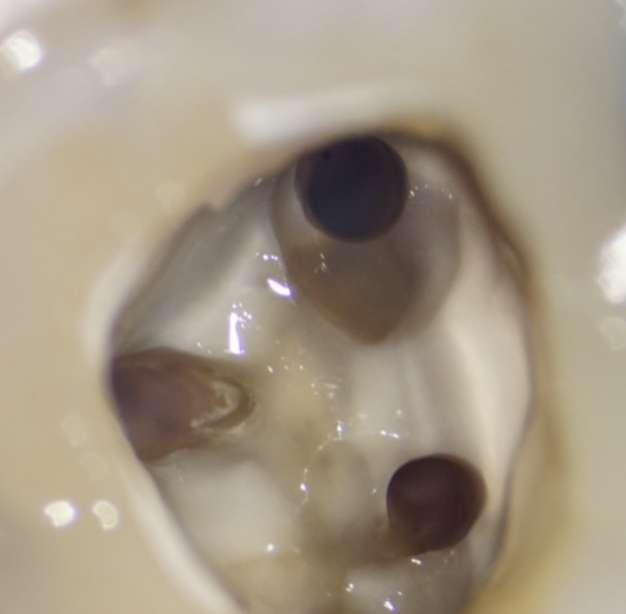

Die Revisionsbehandlung erfolgte in zwei Sitzungen. Nach Anlegen des Kofferdams wurde die provisorische Füllung entfernt und die Zugangskavität gereinigt. Im Anschluss erfolgte die intrakoronale Diagnostik (Abbildung 11). Es zeigte sich bakteriell besiedeltes Wurzelfüllmaterial im mesiobukkalen, distobukkalen und palatinalen Kanal. Das Orifizium des mesiobukkalen Kanals war in palatinaler Richtung erweitert. Die Entfernung eines mesialen Dentinüberhangs mit langschaftigen Rosenbohrern legte das weit nach palatinal verlagerte Orifizium des zweiten mesiobukkalen Kanals frei. Die Entfernung des Wurzelfüllmaterials erfolgte mithilfe von EdgeFile X7 der Größe 25.06, und 17.06 in Crown Down Technik um die Verschleppung von Keimen und bakteriell besiedeltem Wurzelfüllmaterial nach apikal zu reduzieren. Die Erschließung und initiale Aufbereitung des zweiten mesiobukkalen Kanals wurde mithilfe der EdgeFile X7 der Größe 17.04, 17.06 in alternierender Weise wie oben beschrieben durchgeführt. Nach elektrometrischer Bestimmung der Arbeitslänge aller Kanäle wurde die Präparation mit EdgeFile X7 auf voller Arbeitslänge fortgesetzt. Im ersten mesiobukkalen Kanal, distobukkal und palatinal wurde die Aufbereitung mit EdgeFile X7 der Größe 40.06 abgeschlossen, während der zweite mesiobukkal Kanal bis 30.06 aufbereitet wurde (Abbildung 13).

Abbildung 11: Nach Ausarbeiten der primären Zugangskavität; Darstellung des mb2 in der Nähe des palatinalen Kanals